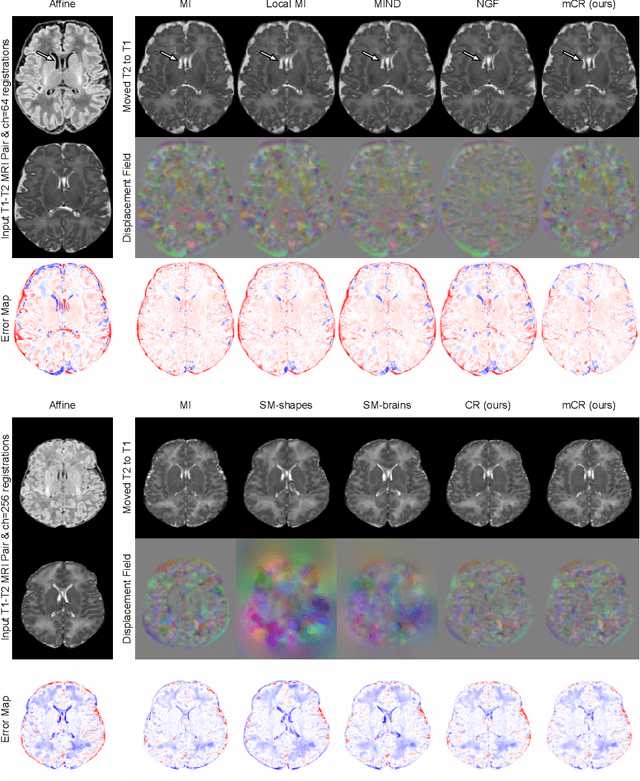

Establishing voxelwise semantic correspondence across distinct imaging modalities is a foundational yet formidable computer vision task. Current multi-modality registration techniques maximize hand-crafted inter-domain similarity functions, are limited in modeling nonlinear intensity-relationships and deformations, and may require significant re-engineering or underperform on new tasks, datasets, and domain pairs. This work presents ContraReg, an unsupervised contrastive representation learning approach to multi-modality deformable registration. By projecting learned multi-scale local patch features onto a jointly learned inter-domain embedding space, ContraReg obtains representations useful for non-rigid multi-modality alignment. Experimentally, ContraReg achieves accurate and robust results with smooth and invertible deformations across a series of baselines and ablations on a neonatal T1-T2 brain MRI registration task with all methods validated over a wide range of deformation regularization strengths.